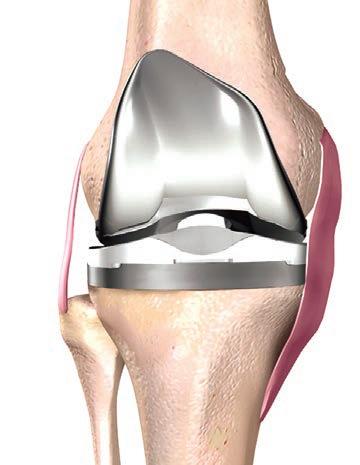

43 TKR – better outcomes Dr Gavin Clark 53 Colorectal cancer & radiation therapy Dr Eve Tiong 54 ACL Rehab – is it all in your head? Dr Casey Whife 39 MCA’s ripple effect Bruce Langoulant 61 Lasers & vascular lesions Dr Ian Skinner 37 Spinal cord treatment on the brink Emeritus Professor Byron Kakulas 59 Physical activity after COVID-19 Olivia Reynolds 56 Sickle Cell Disease Natalie Gamble-Williams & Dr Tina Carter 44 Foot surgery & total ankle replacement Dr Simon Zilko 47 Breast imaging Dr Vanessa AtienzaHipolito 49 First-time shoulder dislocations Dr David Graham Guest Columns This magazine has been printed using solar electricity, and the paper from plantation-based timber has been manufactured and printed with ISO 14001 accreditation, the highest environmental standard. MAJOR PARTNERS 36 Early language issues Dr Sam Calder & Dr Lizz Hill